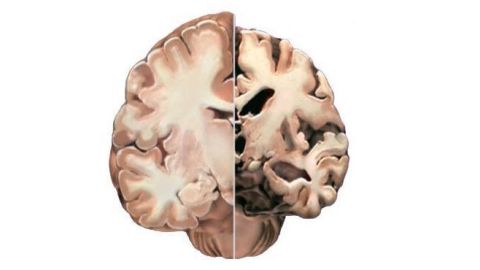

“For reasons we don’t understand, in certain regions of the brain, it changes its shape,” says Gandy. The amyloid proteins form clumps that are poisonous to nerve cells. This poisoning of the brain from amyloid—known as the amyloid hypothesis—is a prevailing theory as to how the disease dissolves neurons, clogging the brain with the debris of dead cells. This, in turn, leads to dementia and eventually to death.

Those individuals who have been found with amyloid buildups in the brain but without dementia are, at least for a time, able to resist this amyloid toxicity, says Gandy. This happens through a system where the brain compensates, engaging other, new and more parts of its structure to perform a task which once took a localized part of the brain.